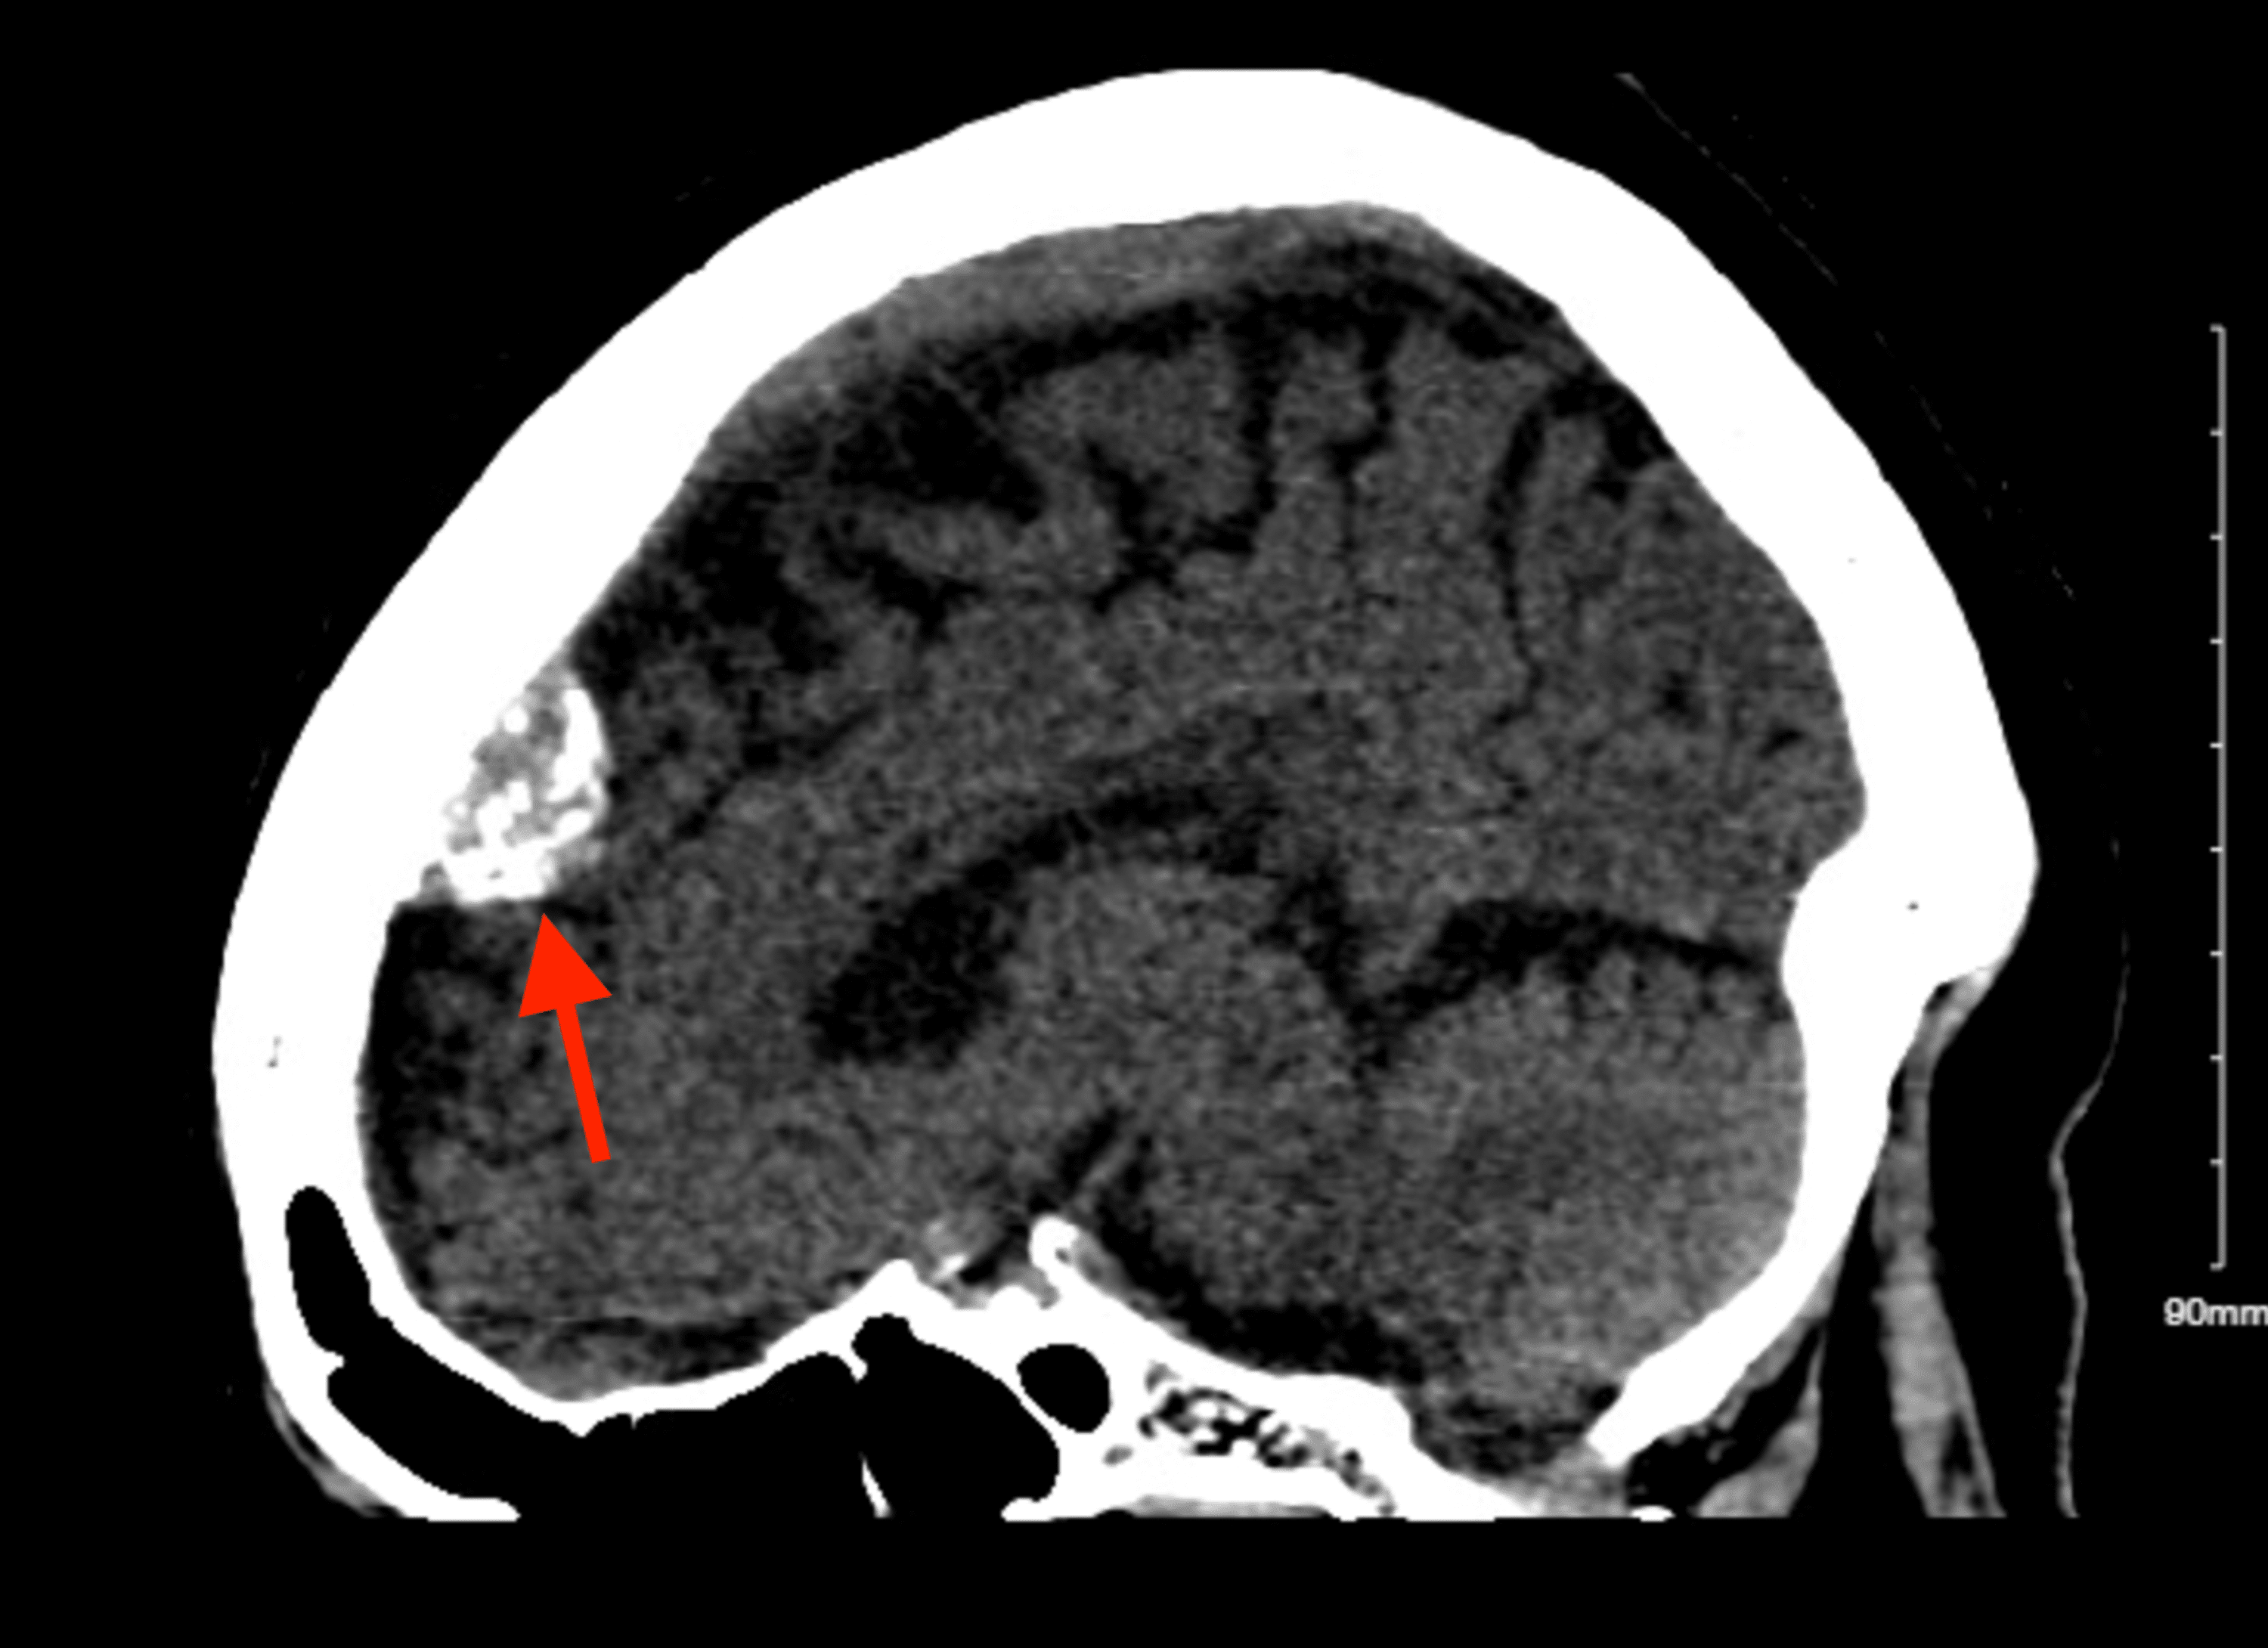

Large meningioma, MRI Stock Image C058/4482 Science Photo Library

Large meningioma, MRI Stock Image C058/4475 Science Photo Library Velum Interpositum Meningioma meningiomas of the third ventricle are a rare subtype of pineal region tumor that arise from the posterior portion. meningiomas of the third ventricle are a rare subtype of pineal region tumor that arise from the posterior portion. we report the first case of velum interpositum meningioma arising from the superior leaflet and give a potential. . Velum Interpositum Meningioma.